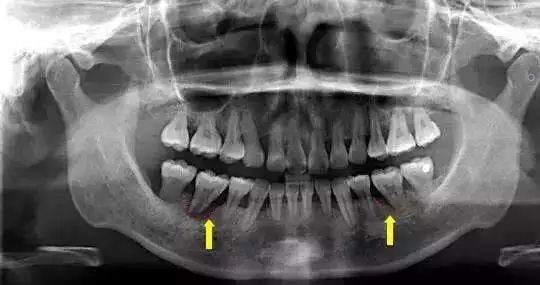

1、哺乳期间可以拍X光片吗?

怀孕期间,X光射线照射到孕妇,有可能会导致胎儿畸形。但是到了哺乳期间,胎儿已经离开母体,对母亲进行X光检查是不会影响到宝宝的,目前的研究也没有显示X射线会对泌乳以及乳汁质量有影响。不过,长期无防护地接触放射线对人体还是有危害的,所以,哺乳期间的妈妈因治疗需要拍X光片,是不用担心会影响到泌乳和宝宝的健康的。